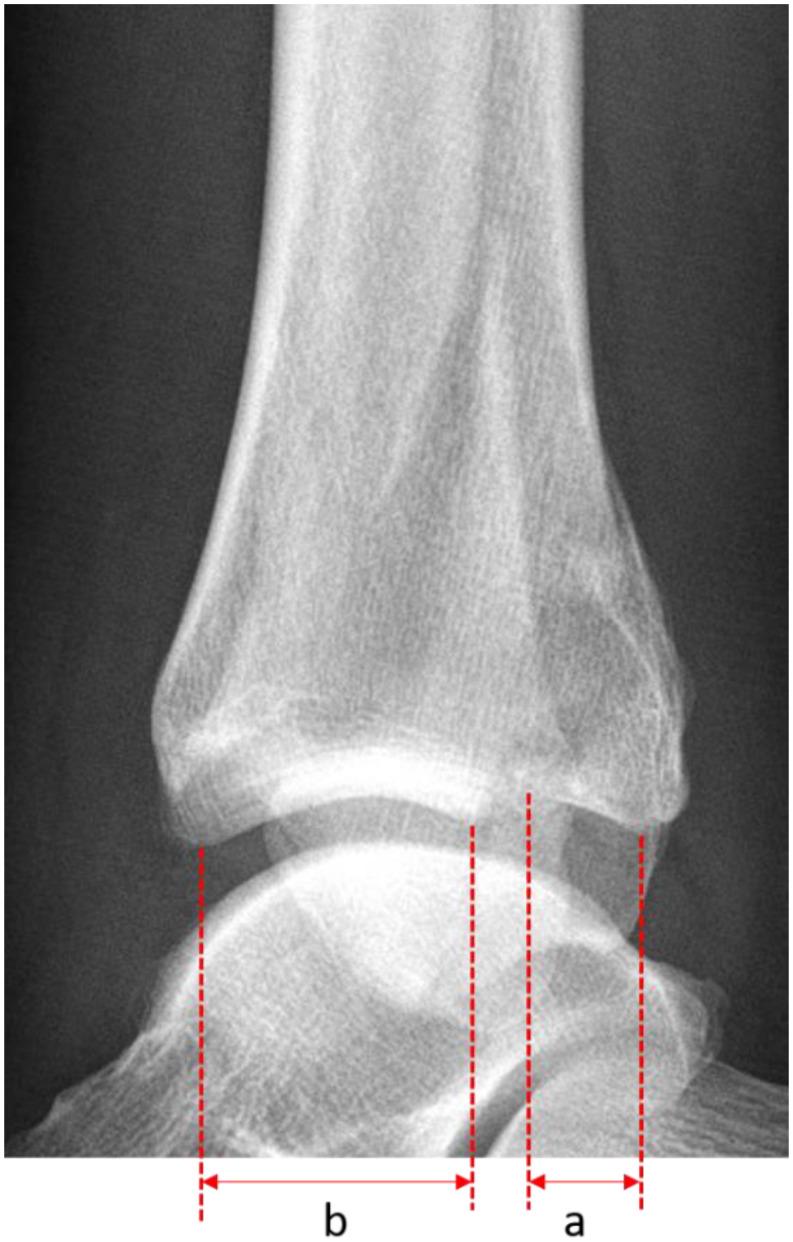

We included 69 consecutive patients undergoing operation for a trimalleolar fracture between 2008 and 2013. Mean follow-up was 11.3 years. Patients completed the SF-12 and EFAS scores. Radiological osteoarthritis (OA) was assessed using the Kellgren-Lawrence classification. Postoperative complications were classified according to Sink. PMF size was measured on preoperative x-ray and CT and classified according to the Haraguchi classification.

我们纳入了2008年至2013年间连续69例接受三踝骨折手术的患者。平均随访时间为11.3年。患者完成了SF-12和EFAS评分。使用Kellgren-Lawrence分类评估影像学骨关节炎(OA)。术后并发症根据Sink分类。术前通过X线和CT测量PMF大小,并根据Haraguchi分类进行分级。